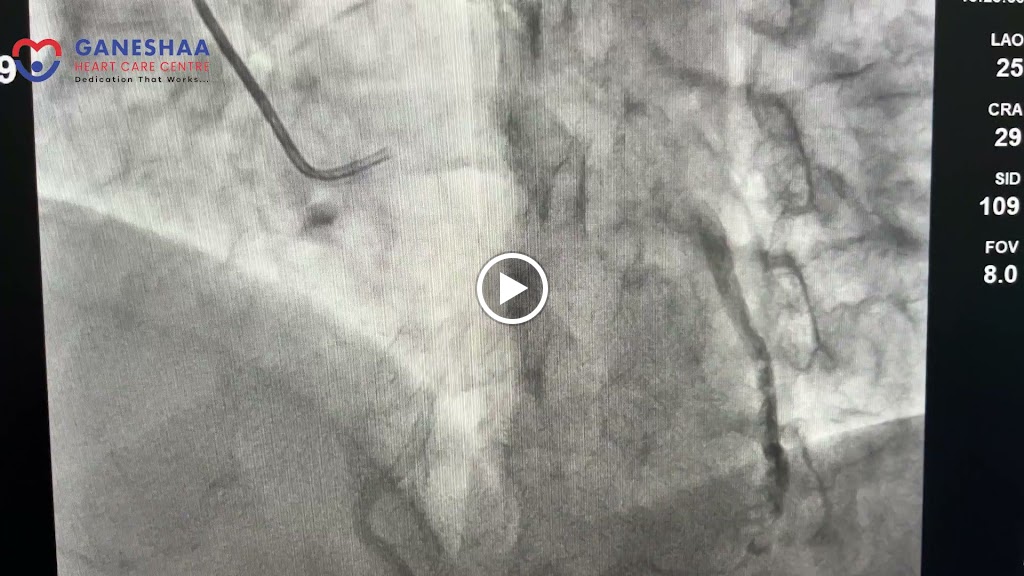

Ganeshaa heart care centre is a dedicated cardiac hospital in Nagpur. At Ganeshaa we have ICCU, operation theatre and rooms. We have a well-equipped and highly advanced flat panel ceiling mounted Schimadzu Cath lab with IVUS, FFR and Rota ablation facility. We have advanced 2 D ECHO machine of Philips affinity series with auto strain LV and DSE protocol. We also have TMT, Holter and ABPM facility at our centre. At Ganeshaa heart care we aim to provide quality care to our patients with full dedication, integrity, honesty and compassion at affordable cost. Our mission is to establish a bond of trust with our patients and their relatives by doing excellent work in the field of cardiology. Best cardiology hospital in Nagpur city.

On 23rd December my 72 years old father sustained Anterior Wall Myocardial Infarction with severe shock. Even after being late in night to get admitted at Ganesha Hospital Dr. Rhishikesh Umalkar Sir Promptly done Rescue Angioplasty removed 100% block on LAD and Very Empathitically took care and able to discharge within 4 days from Hospital. We are very grateful towards Ganesha Heart care for saving my father's Life.